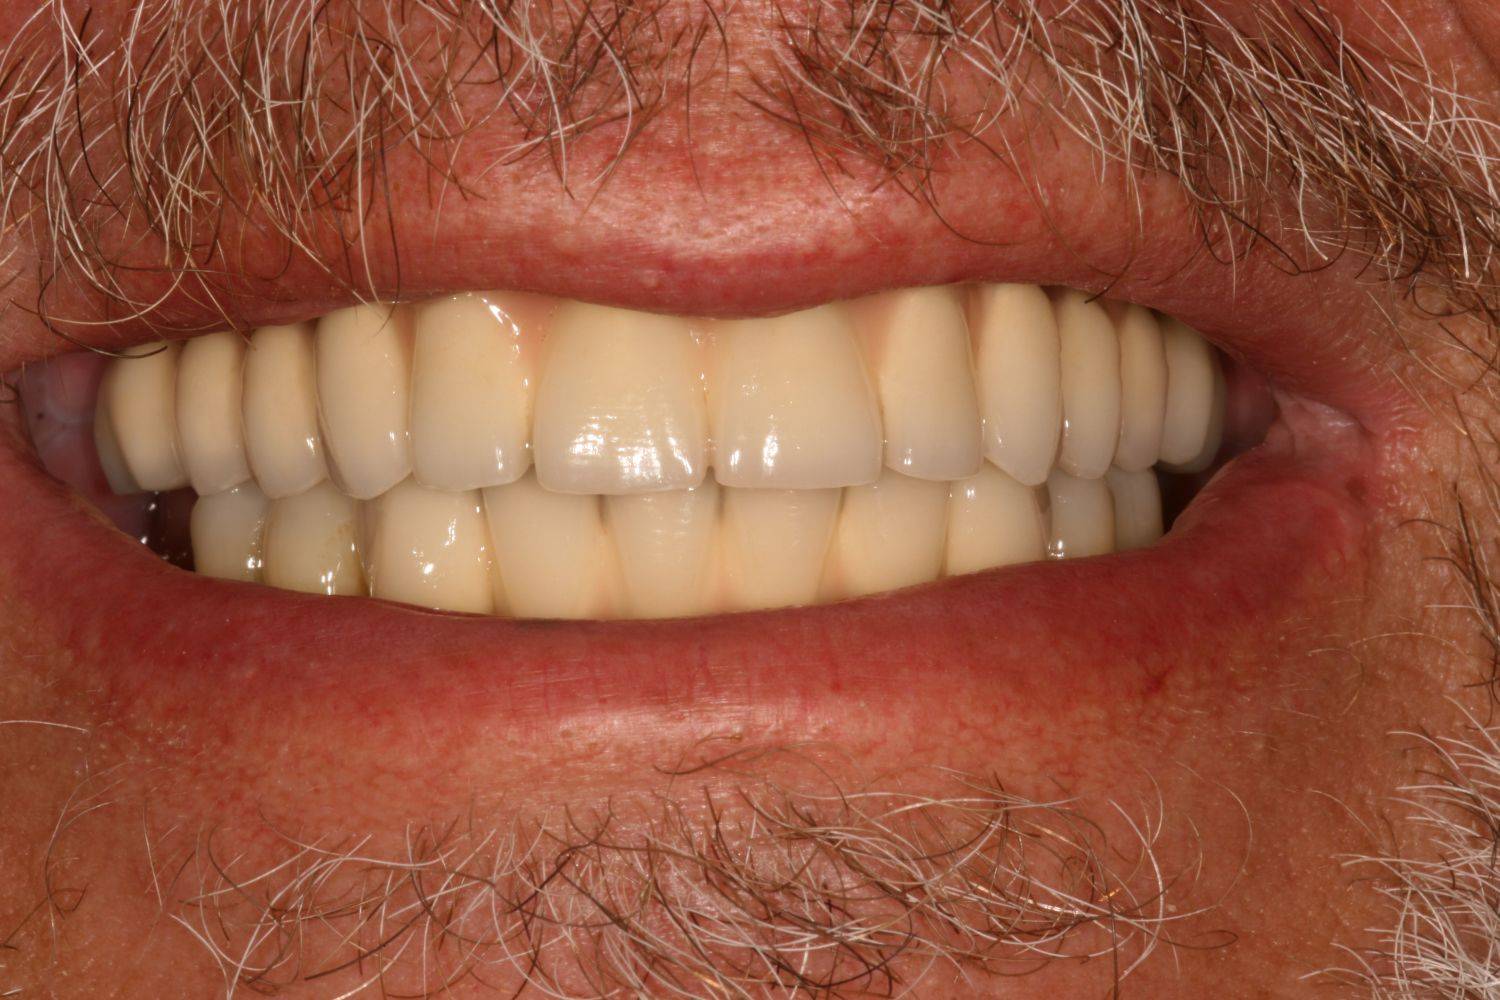

5. eset

Ennek a kedves hölgynek 20 éves álmát váltottuk valóra. 20 évig hordott kivehető fogsorokat. 12 implantátum beültetése után alsó és felső fixen rögzített hidakat készítettünk. Nincs többé kivehető - evéskor, beszéd közben - elmozduló fogsor. Javult a rágási hatékonyság is, amely az egészséges táplálkozás szempontjából is nagyon fontos tényező.